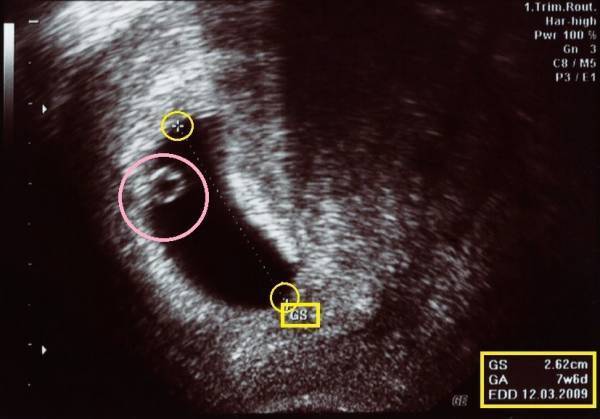

妊娠初期の超音波画像

これは妊娠初期の超音波画像です。中央の黒い楕円形をした部分が「GS(胎嚢=赤ちゃんが入っている袋)」で、ピンク色の○の中にいるのが胎芽(赤ちゃん)です。黄色い○で囲んだ「+」から「+」の部分で、胎嚢の大きさを測っています。この画像の胎嚢の大きさは右端の黄色い四角の中に、2.62cmと出ていますね。

その下の「GA」は在胎期間(gestational age)のこと。

赤ちゃんがおなかの中にいる週数で、予定日から計算しています。「7w6d」とは妊娠7週6日相当の大きさだということです。一番下の「EDD」は、分娩予定日(Expected date of delivery)です。分娩予定日は「EDC(expected date of confinement)」と表記されていることもあります。